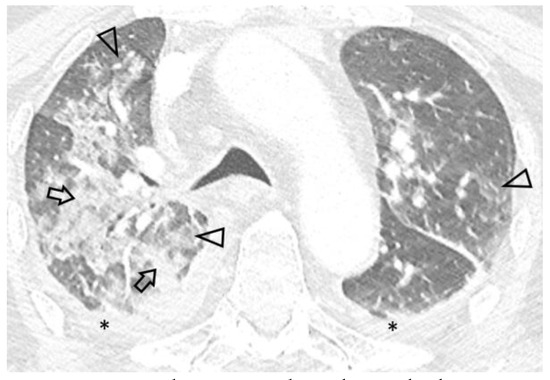

Due to worsening hypoxemic respiratory failure, the patient was transferred to our hospital’s ICU. On admission the patient was febrile (38.3°C), hemodynamically unstable (arterial blood pressure 90/65 mmHg) and in respiratory distress, with bilateral inspiratory rales. Arterial blood gas analysis revealed hypoxemia with respiratory alkalosis (FiO2 0.50, pH 7.46, partial pressure of oxygen 58 mmHg, partial pressure of carbon dioxide 33 mmHg, HCO3 23 mmol/L). Laboratory tests revealed pancytopenia (hemoglobin 11.8 g/dL, white blood cells 3200/μL, platelets 54000/μL), increased C-reactive protein (15.9 mg/dL) and procalcitonin (1.11 ng/mL) levels, hematuria, leukocyturia and mild proteinuria. Serological tests for viral hepatitis and human immunodeficiency virus were negative, as well as markers of immune-mediated disease (antinuclear, anti-neutrophil cytoplasmic, anti-glomerular basement membrane and anti-streptolysin O antibodies), while remaining laboratory findings were unremarkable. Chest X-ray on admission showed ill-defined alveolar infiltrates, while thoracic CT demonstrated extensive ground-glass opacities, as well as localized alveolar opacities of all lobes with a predominant peri-broncho-vascular distribution (Figure 1). Small pleural effusions were also noted. Differential diagnosis based on imaging and provided history mainly included a) acute respiratory distress syndrome due to complicated UTI, b) pulmonary infection and c) BCG-related complication.

Figure 1.

Axial 0.6 mm slice through the upper lung fields demonstrates asymmetric ground glass (arrowheads) and alveolar (arrows) opacities with a centrilobular distribution. Bilateral pleural effusion (*) is also seen.